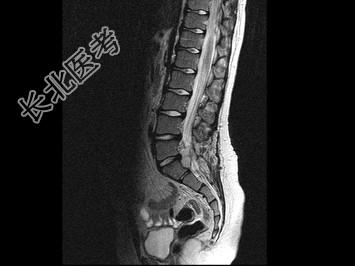

- 单项选择题男,8岁, 左髋疼痛,跛行1月余, 结合MRI检查,最可能的诊断是 ( )

A、骶部神经鞘瘤

B、室管膜瘤

C、神经纤维瘤

D、脊膜瘤

E、脊髓空洞症